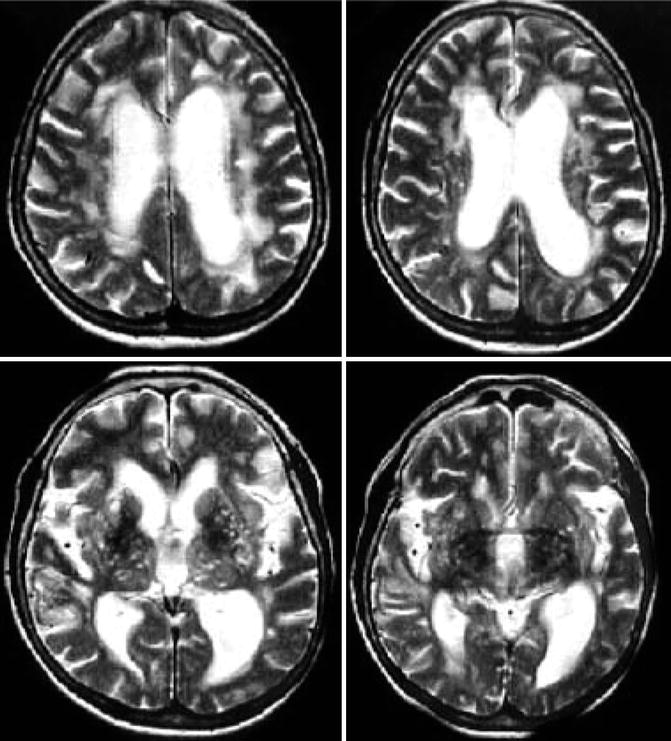

Hydrocephalus MRI – wikidoc

MRI of hydrocephalus – Stock Image – M170/0370 – Science Photo Library

Hydrocephalus MRI – wikidoc